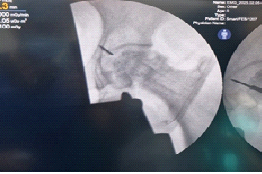

Subsequent attempts to free the broken tip using a thicker guidewire inadvertently pushed it further toward the joint cavity. Eventually, it was visualized to be lodged in the acetabulum on fluoroscopy. To retrieve the broken wire, the remaining part of the guidewire was aligned with the broken tip (Fig. 2) over which a dynamic hip screw inner reamer was gently hand-reamed (Fig. 3). This made sure the reaming did not create another tract. This maneuver facilitated mobilization of the wire but also pushed it further (Fig. 4). Finally, using an arthroscopic grasper under continuous fluoroscopic guidance, the fragment was successfully retrieved (Fig. 5).

Figure 5: Retrieved K-wire tip using arthroscopic grasper.